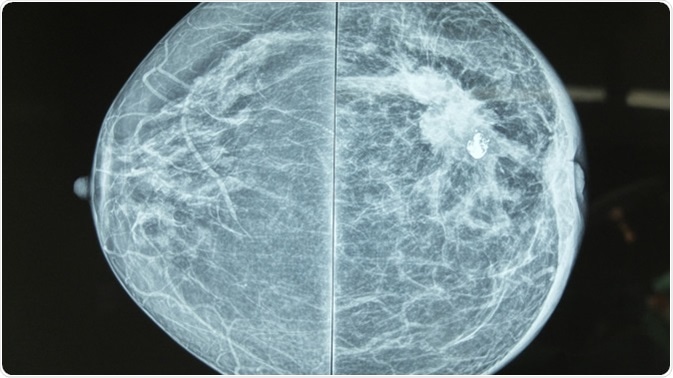

Mammography is a radiographic method which uses low-dose X-rays to image the breast tissue for both screening and diagnosis of breast cancer. Any suspicious high density regions or unusual patterns such as microcalcifications are examined carefully. These could be due to a range of abnormalities, such as tumors (benign and malignant), fibroadenomas, or cysts with solid areas.

Mammography image showing left breast calcification to suggest malignancy. Image Credit: Casa Nayafana / Shutterstock